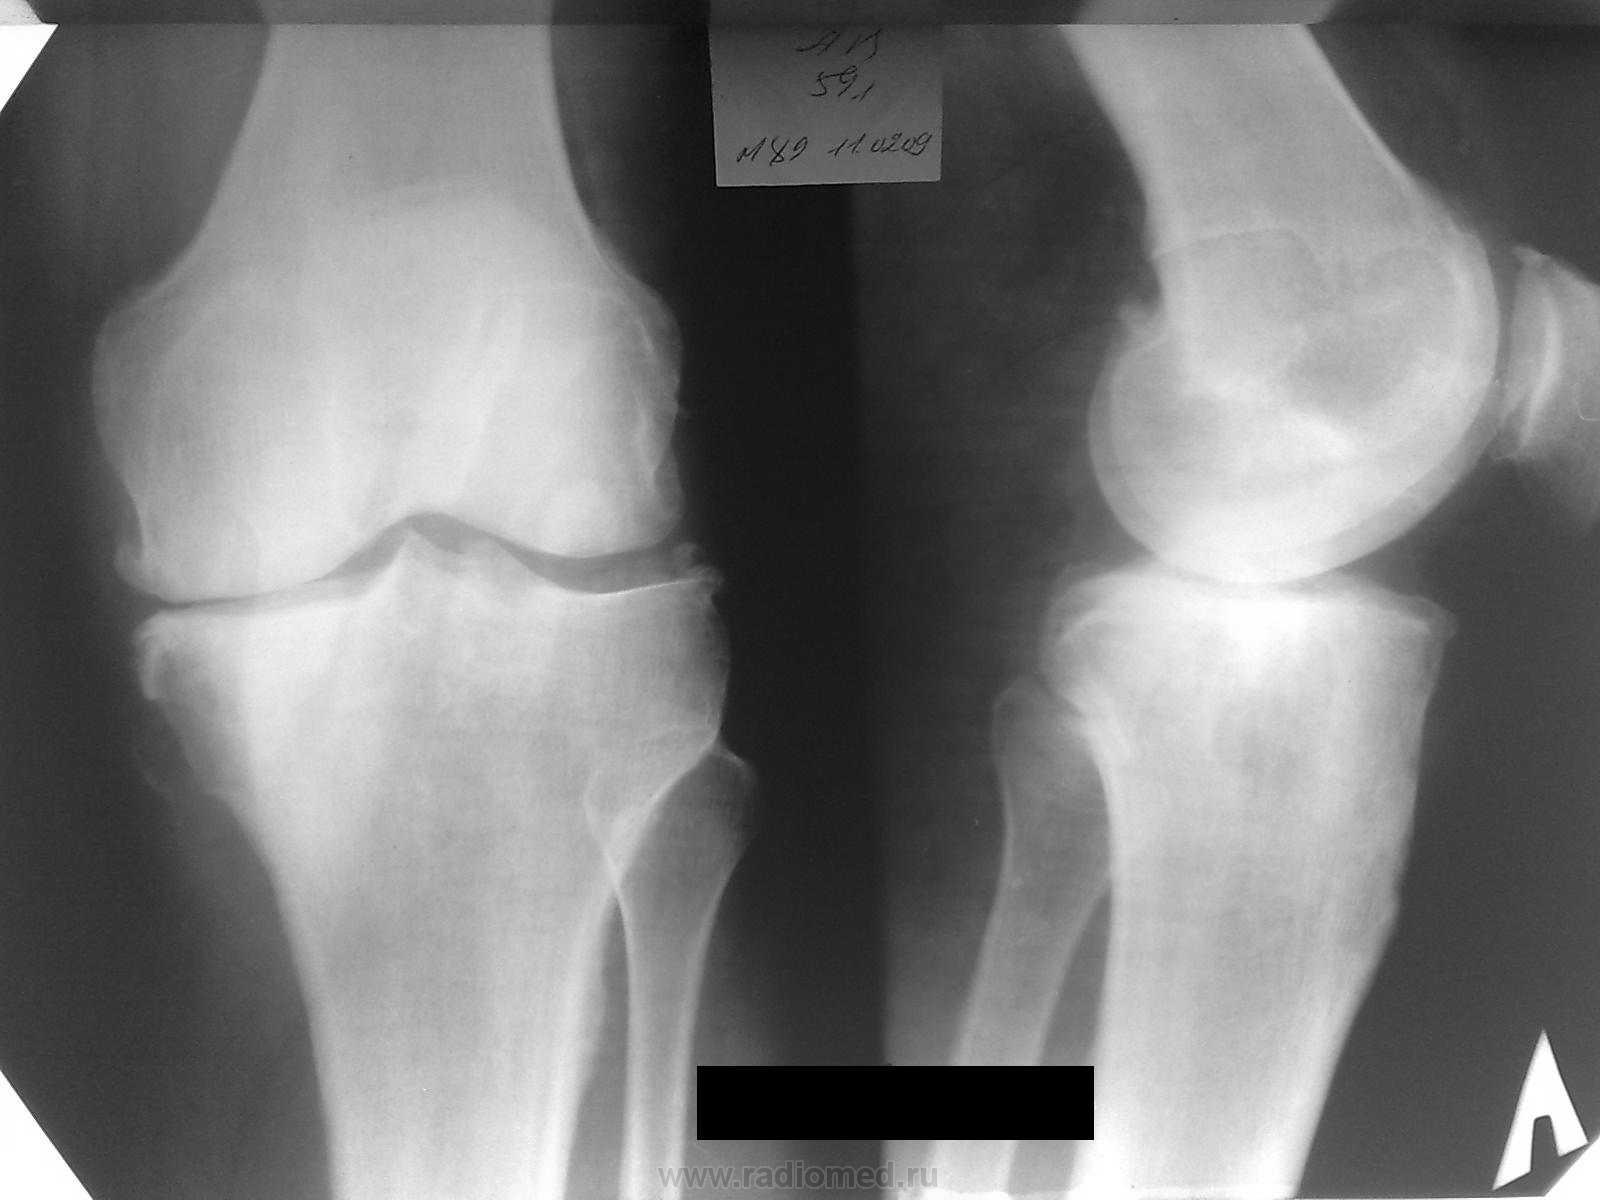

Пациентка жалуется на боль в обл. внутр. мыщелка б.берц кости. Снимки мерзкого качества, но это все, что есть, временной интервал - около года (9 - 10 гг). Прилагаю КТ на пленке. Наша версия - периостальная липома (ангиолипома, миксома).  Публикую не только как интересный случай, но и для консультации. Аналогичное сообщение размещено на радиографии.